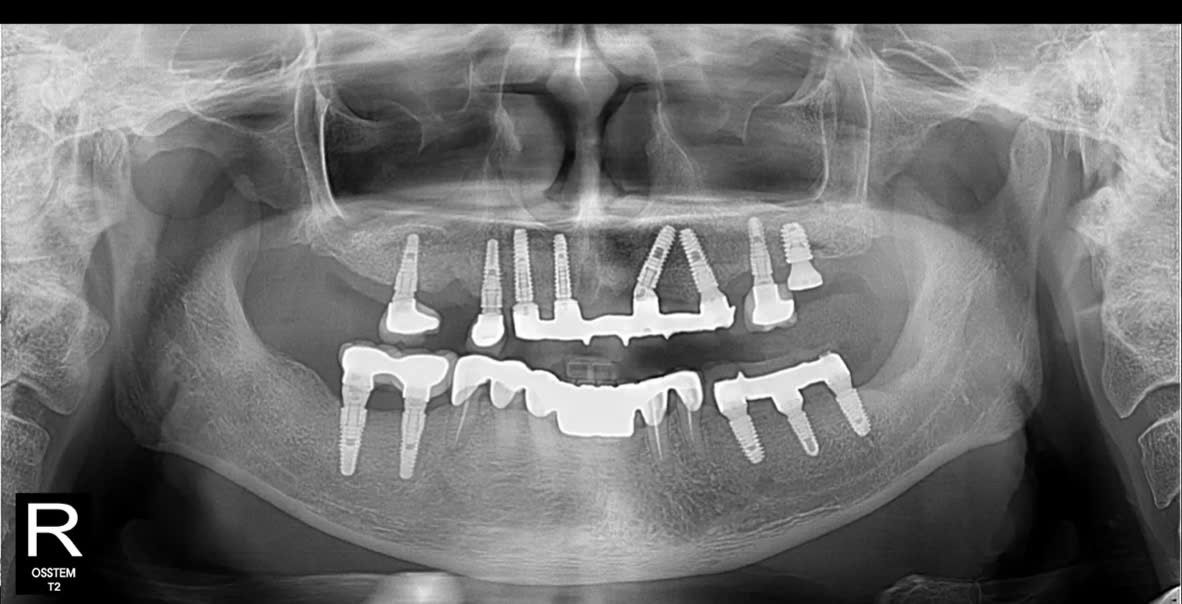

- Hàm trên: chỉ còn lại vài trụ Implant cũ đã được đặt cách đây hơn 10 năm, hiện nay có dấu hiệu tiêu xương quanh trụ, không còn đảm bảo chức năng nâng đỡ phục hình.

- Hàm dưới: nhiều mão sứ và cầu răng đã xuống cấp, lỏng, gãy, gây mất cân đối khớp cắn và ảnh hưởng đến khả năng ăn nhai.

- Xương hàm có dấu hiệu tiêu và mỏng, cần được đánh giá kỹ qua phim CT ConeBeam 3D để xác định có cần ghép xương, nâng xoang trước khi cắm trụ mới.

- Hàm trên: Cấy ghép Implant toàn hàm bằng kỹ thuật All-on-5 – giải pháp phục hồi tối ưu giúp tái tạo toàn bộ hàm răng trên chỉ với 5 trụ Implant, mang lại độ vững chắc và thẩm mỹ cao.

- Hàm dưới: Đặt thêm Implant Hiossen (Mỹ) để phục hình lại các răng mất, đảm bảo khả năng chịu lực tốt, tích hợp xương nhanh và tuổi thọ lâu dài.